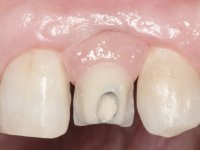

• Placement of an implant at the tooth site 2.2. Rehabilitation of the implant with a coronary and gingival component abutment. in which the screw access hole was "camouflaged" with a feldspathic veneer.

This addition of resin would guide the ceramist in the final placement of the gingival tonality ceramic. The crown that would rehabilitate tooth 1.3 was cemented in this test session with glass ionomer cement, reinforced with composite resin. Once the laboratory work was finished on the veneer for tooth 1.2, the abutment, and the veneer for the implant, this was bonded in the mouth, after placement of the absolute insulation. The work completely satisfied the patient. For eight years, the patient had periodical check-ups, and was pleased with the treatment, but also began to show interest in an aesthetical intervention on the upper central incisors. Once the second phase of our intervention was decided, dental preparation of teeth 1.1 and 2.1 was performed for the placement of two feldspathic veneers. Particular care was taken in the distal inter-proximal preparation adjacent to the abutment of the implant.

The axis of insertion of the veneer in relation to the abutment was very carefully evaluated. The feldspathic veneers were prepared in the laboratory and then bonded to the mouth after placing absolute insulation. One year later, we began our third phase of treatment, after the veneer in tooth 2.1 fractured. A dental preparation was done on the bonded veneer, seeking to extend the distal inter-proximal interface more to the palate. The objective would be to move the veneer to a more palatine contact point. Preparation of tooth 1.2 was limited to creating an insertion axis. After preparation, the total crown and laboratory veneer were bonded to the mouth. First, the crown was bonded using a relative insulation with Teflon, later the veneer was bonded after the absolute insulation placement. In the crown, I used this type of insulation to avoid the use of staples. It would be difficult to apply due to the shape and size of the tooth, and would also be aggressive to the soft tissues. After bonding procedures, the occlusal integration of the work was evaluated.